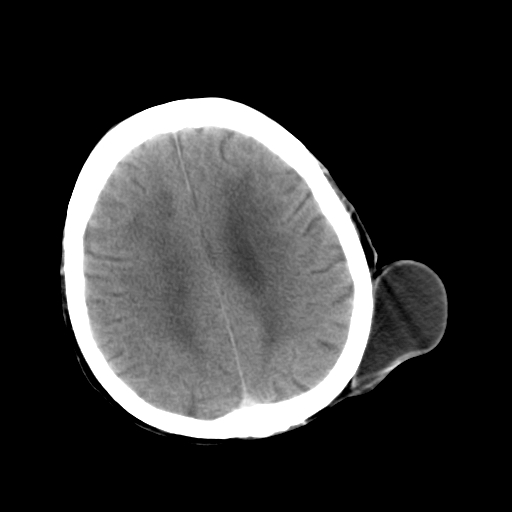

标题: CT25147:男,62岁,右侧肢体活动障碍不灵活三天。 [打印本页]

男,62岁,右侧肢体活动障碍不灵活三天,左侧头皮肿物十余年(ct值8hu)。

多发腔梗!皮下脂肪瘤!

1)多发性腔隙性脑梗塞。2)脑白质病。3)脑萎缩。4)左侧枕顶部头皮下皮样囊肿,不排除脂肪瘤。